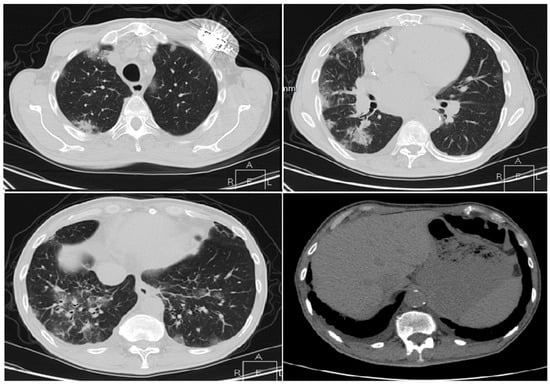

3.1.1. Cases Reports from Iran

Case 1

Case 2

Case 3

Case 4

Case 5